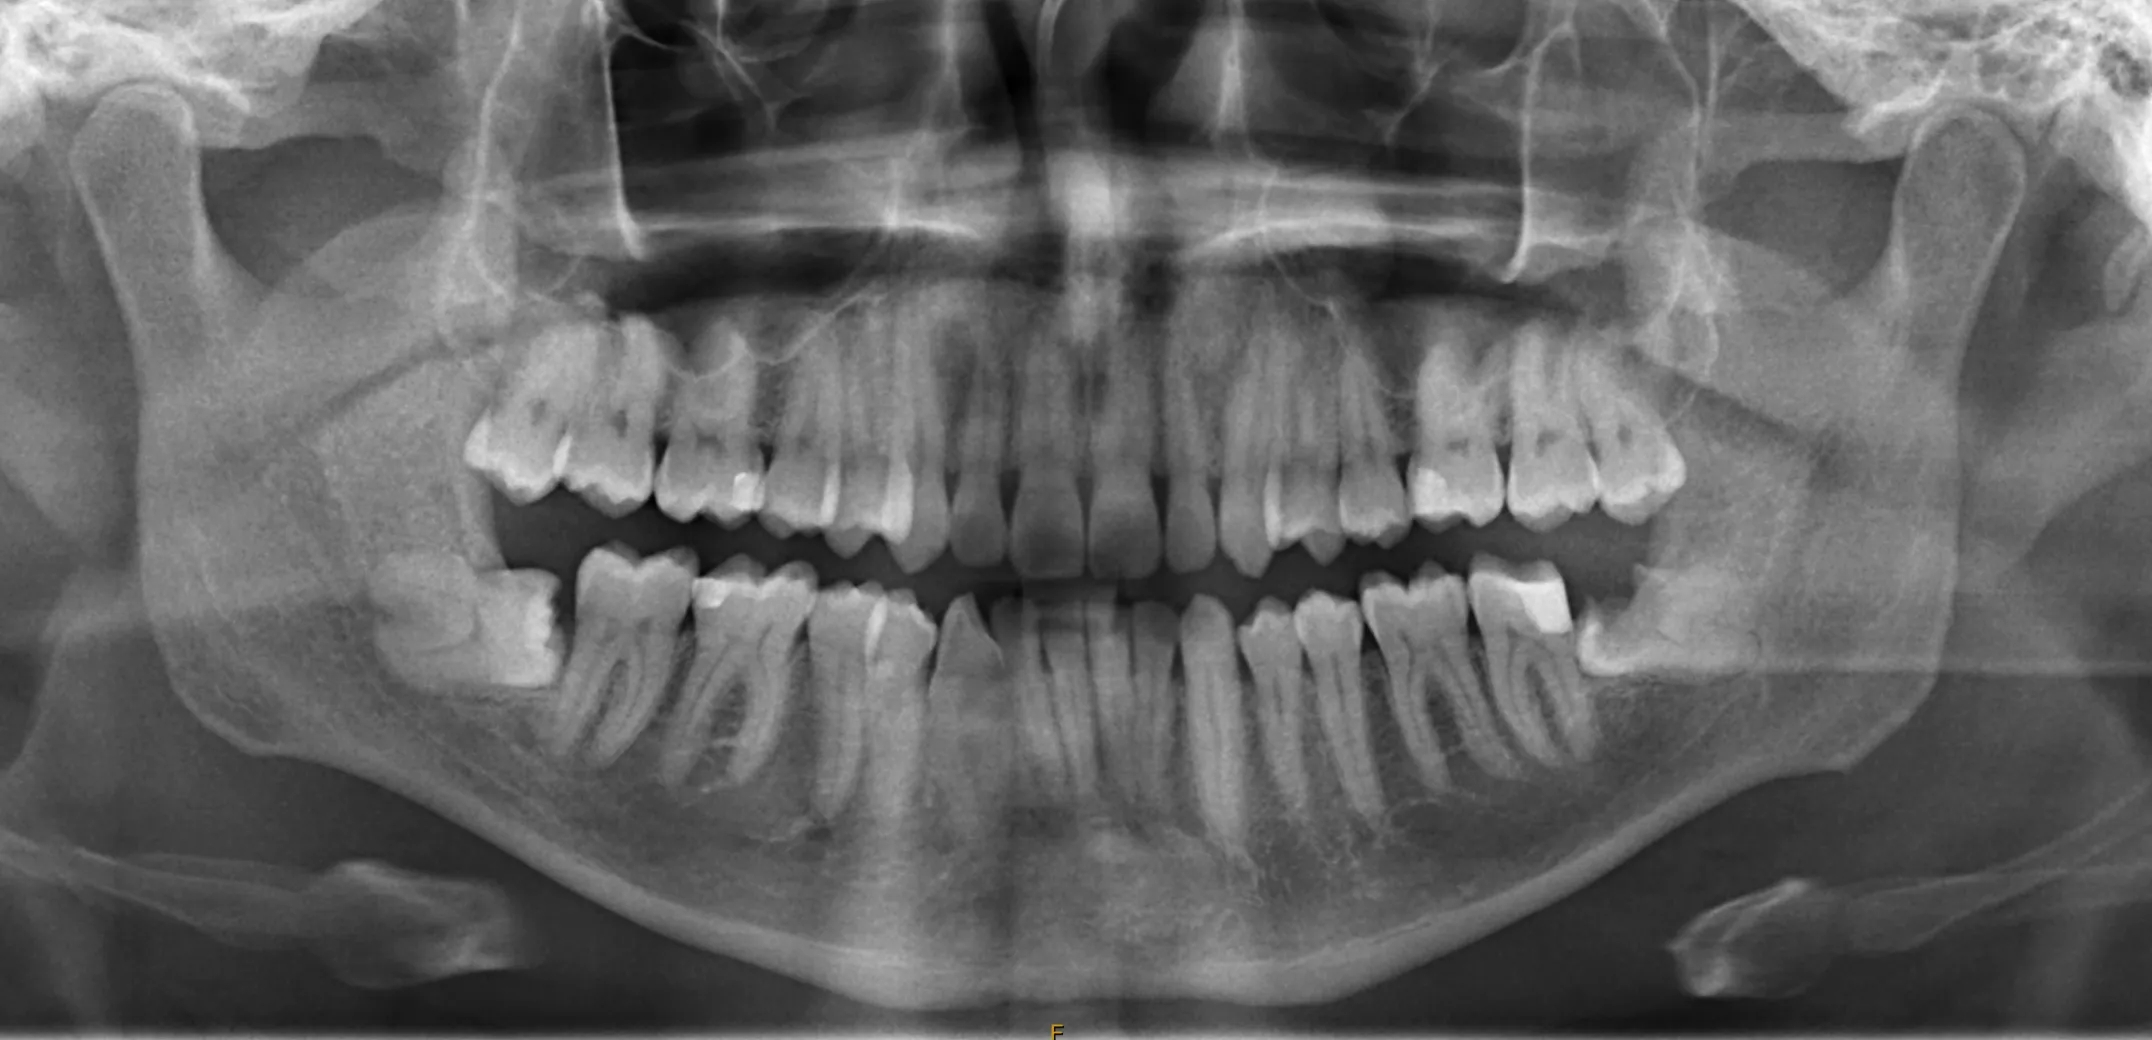

- Referral and Imaging: The process begins with a referral from your dentist, along with a recent OPG X-ray. Dr Henze’s team can arrange a request form for you to have this completed at SKG Radiology. An appointment is not required for the OPG. X-rays are used to assess the position and condition of the wisdom teeth.